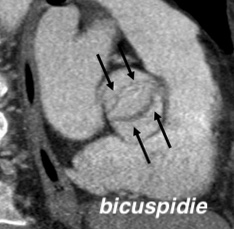

- Autre cause plus rare: Bicuspidie Aortique

- Une autre cause plus rare: Bicuspide Aortique, Endocardite, RAA